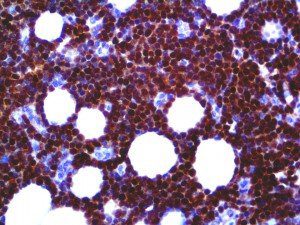

It is the ICU physician who is most likely to witness one of the deadliest manifestations of the abnormal immunological response, the cytokine storm syndrome (CSS). This response is also referred to by some as the cytokine release syndrome (CRS). CSS is characterized by continuous activation and expansion of macrophage and lymphocyte populations, which secrete large amounts of cytokines, causing the cytokine storm. This massive cytokine release is akin to hemophagocytic lymphohistiocytosis (HLH) disease, a syndrome characterized by initial unchecked and persistent activation of cytotoxic T lymphocytes and NK cells.

Clinical and laboratory manifestations of HLH include fever, enlarged liver and/or spleen, neurologic dysfunction, coagulopathy, liver dysfunction, cytopenias (i.e., low levels of erythrocytes, leukocytes, and/or platelets), hypertriglyceridemia, hyperferritinemia, hemophagocytosis, and eventually diminished NK cell activity as the immune system becomes progressively paralyzed. HLH can be familial (primary HLH) or secondary to another disease process (sHLH), such as rheumatic disease, in which it is referred to as macrophage activation syndrome (MAS, characterized by elevated ferritin).